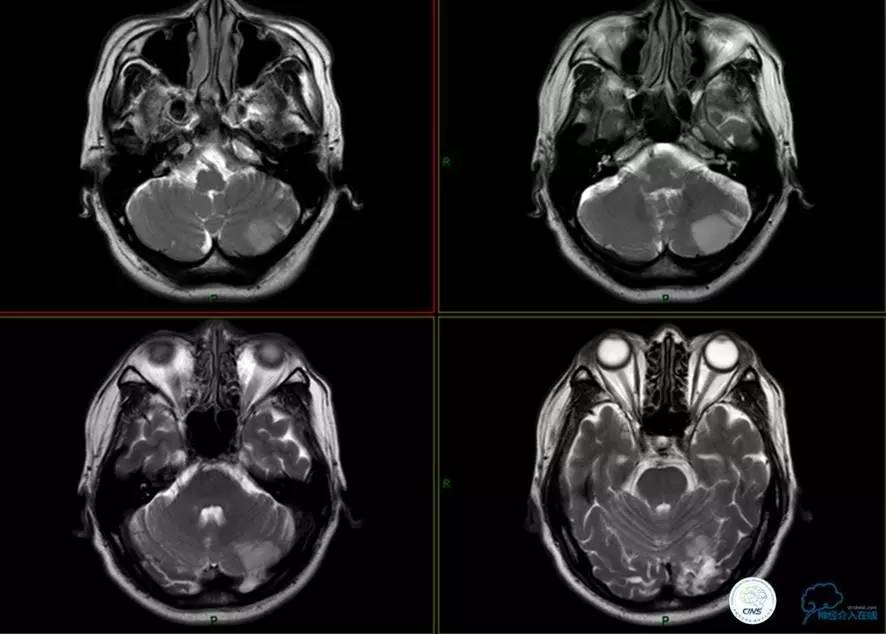

▼头颅MR

▼入院MR